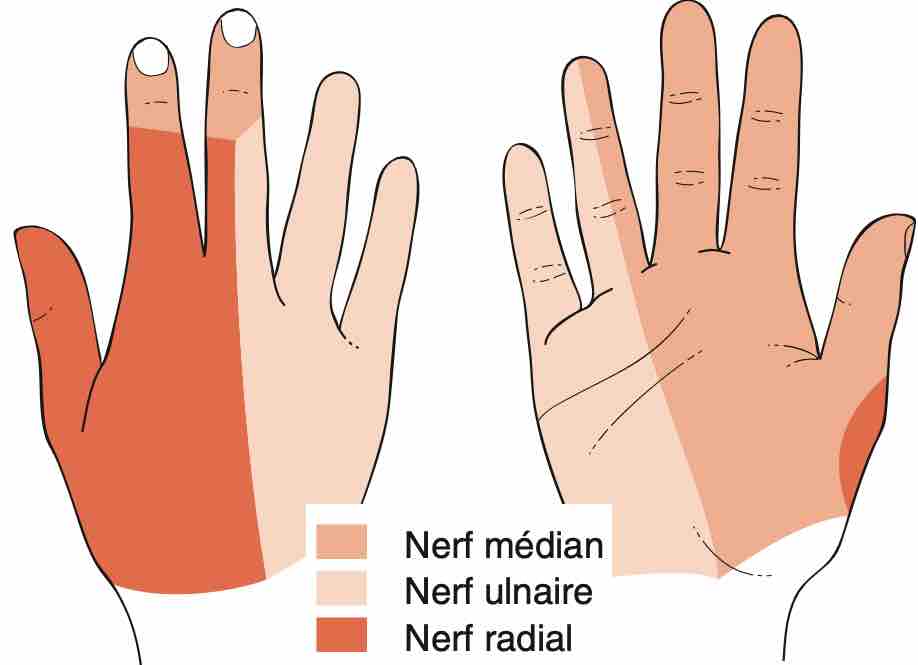

Pas d'anomalie des nerfs médian et ulnaire au poignet.

Aspect normal du nerf ulnaire dans son tunnel.

Nerf ulnaire

Nerf ulnaire en place au sein de la gouttière épitrochléo-olécrânienne.

Aspect fasciculaire sans disparité de calibre ni augmentation de sa surface de section.